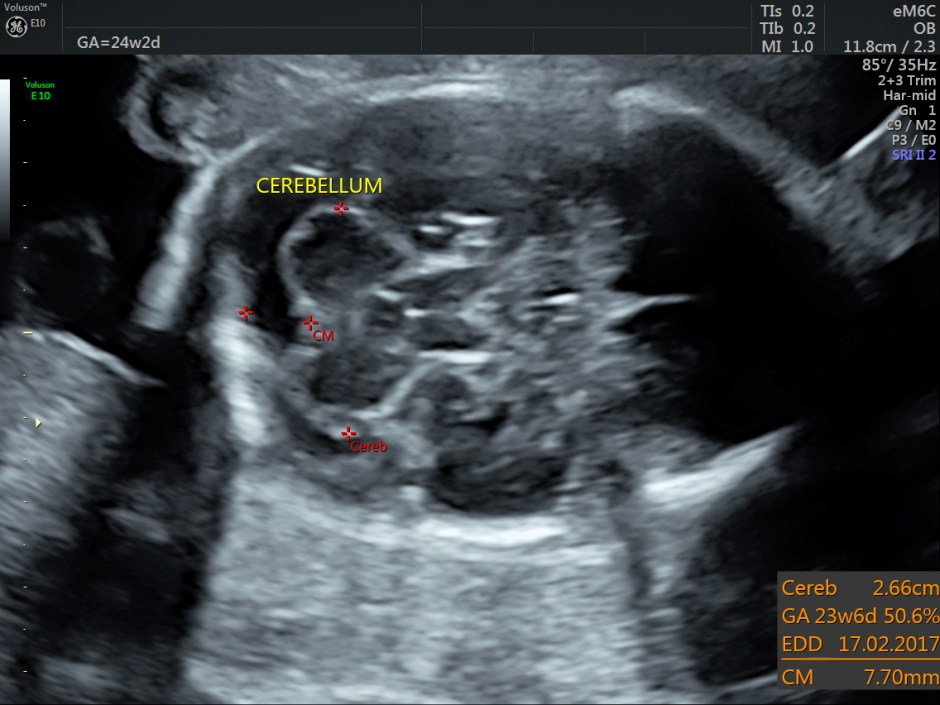

Some reconstructed images are given below.